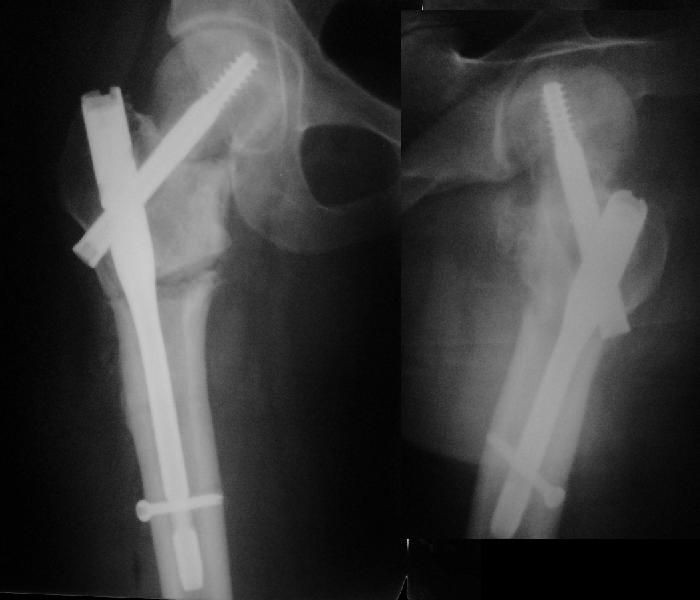

Учитывая возраст больного и качество кости, я однозначно за остеосинтез. Можно обойтись и без остеотомии, линия излома не вертикальная. Возможно с костной аутопластикой для стимуляции. Только отрепонировать хорошо, на представленных снимках, перелом недорепонирован, есть ротационное смещение. Плюс винт биомеханически введен не совсем удачно.

на представленных рентгенограммах прослеживается линия резорбции вокруг введенного винта, что свидетел ствует о нестабильности произведенного остеосинтеза ии отсутствии консолидации перелома. На мой взгляд нужно произвести ркт исследование и выполнить при отсутствии консолидации реостеосинтез с костной аутопластикой. При отсутствии сращения после данной операции остается ввариант с эндопротезированием. Выполнить репозицию несросшегося перелома закрытым способом на мой взгляд не совсем реально, открытая репозиция чревата аваскулярным некрозом. Выполнение вальгизирующей остеотомии считаю нецелесообразным так как это приведет к увеличению давления на головку (за счет натяжения мышц бедра )6 лишенную нормального кровотока приведет к ее коллабированию. С уважением Даниленко Олег.

Учитывая, что при первичном синтезе DHS репозиция, по всей видимости, была неадекватная, то открывая область перелома для репозии, можно получить аваскулярный некроз головки.

Согласен с Paul, что возможно удаление гвоздя DHS, аутокостное штифтование по ходу гвоздя, и дополнительная фиксация 3 мя компремирующими винтами, что позволит активизировать больного без внешней иммобилизации.

Уважаемый Александр! Что имеем? Судя по представленной Вами информации (Р-граммы и клиника), несмотря на крайне неудовлетворительное стояние отломков имеет место неполное сращение перелома. В противном случае никак не возможна ходьба с тростью, практически полное отсутствие болей, нет и асептического некроза. Отсюда и должны рассматриваться варианты дальнейшей тактики.Эндопротезирование, открытые репозиции, остеотомии вряд ли адекватны имеющейся ситуации.

Никто не обратил внимания, что конструкция-то вся "развинчена" - вывернулся винт из шеечного винта, пластина не прилегает к диафизу. Резорбция кости вокруг шеечного винта не позволит как-нибудь надежно синтезировать вальгизирующую остеотомию, а в случае неудачи сама остотомия осложнит последующее эндопротезирование. Поэтому, думаю, что лучшим вариантом будет синтез аутокостью + канюлированные винты (дабы избежать кокситной повязки).